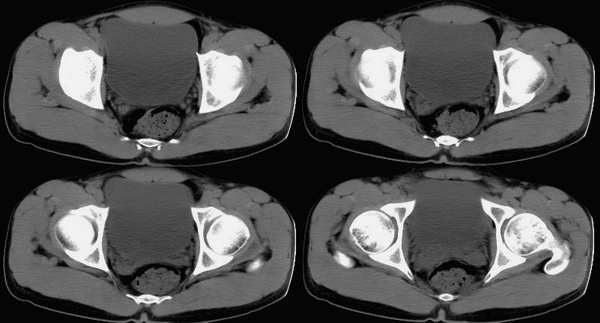

男,25岁,尿血15天,bus示膀胱内囊性占位

请大家仔细观察,病变在这几幅中,只是不一定顺序排列.

膀胱后壁偏右可见一小的囊性低密度影,考虑膀胱憩室可能

右侧输尿管下端囊肿待排,建议i.v.p

膀胱后壁偏右可见一小的囊性低密度影,膀胱前方可见一软组织影,和膀胱分届尚清。膀胱右后壁见一软组织影突向腔内,精囊腺增大。

精囊腺增大,老师好像说过急性精囊腺炎有时会有血尿,请各位前辈指教

右侧输尿管下端囊肿可能性大,建议ivp.

第1\\2图可见右侧输尿管扩张积水,第四\\五图膀胱内右侧精囊腺前方可见枣核样囊影,壁薄均匀,内为水密度.bus和ct均诊断:右侧输尿管末端囊肿,已建议ivp.